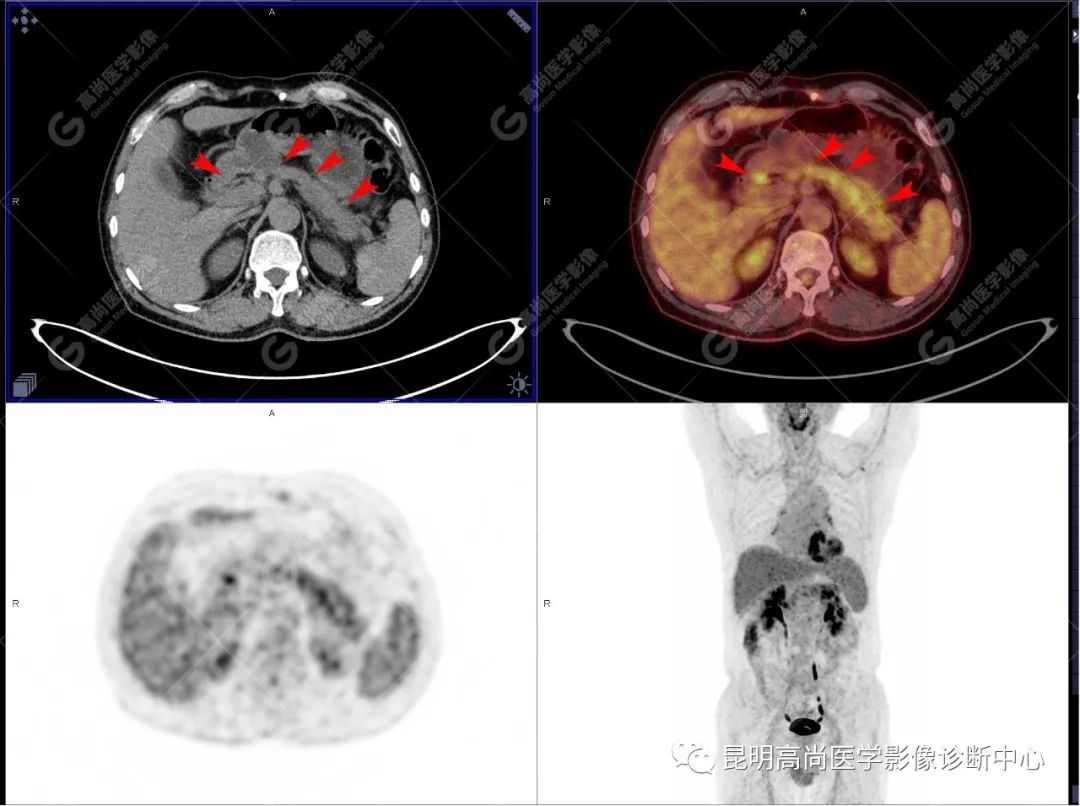

检查图像

影像诊断

十二指肠壶腹区等密度结节影伴糖代谢持续增高,多考虑恶性病变(壶腹癌),继发主胰管扩张及慢性胰腺炎表现;腹膜后多发淋巴结显示,糖代谢不同程度增高,不除外转移。

(1)CT 表现

胰腺局部增大、肿块形成。

胰管阻塞、肿瘤远端的主胰管扩张,甚至形成潴留性囊肿。

胰管、胆总管均受累、扩张,形成「双管征」。

肿瘤侵犯胰腺周围血管及脏器。

增强后强化不明显。

(4)18F-FDG PET/CT

在诊断胰腺癌方面具有较高的敏感性,其敏感性可达 85%~90%,特异性可达 55.6%~94%;尤其在鉴别良恶性的囊性肿瘤时,其准确率可达到 94%~95%;PET/CT 是胰腺癌的主要检查手段,它比常规 CT 和 MRI 更具优势,可早期发现远处转移灶;同时可以作为一个独立的、用于预测胰腺癌生存和无进展生存的独立的指标,即 SUV,代谢肿瘤体积,即 MTV。